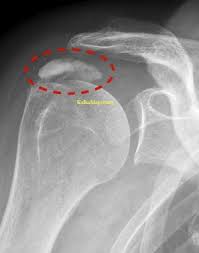

Der Verlauf der Kalkschulter variiert individuell man unterteil die Erkrankung in 4 Stadien. Eingriff dauert 20 Minuten danach ist der Kalk weg. Ob die KK Kosten übernimmt klärt sich morgen.

Meist heilt die Kalkschulter binnen einiger Wochen oder Monaten von allein aus. Alle nicht-operativen Maßnahmen über sechs Monate keine entscheidende Verbesserung erbracht haben sie dauerhaft starke Schmerzen haben die Kalkansammlung mehr als einen Zentimeter beträgt das Kalkdepot eine sehr harte Zusammensetzung aufweist. Man muss gar nicht den kompletten Kalk entfernen damit es abheilen kann bzw.

Die Operation einer Kalkschulter sei eine kurze unkomplizierte Sache sagt Karim Eid. Die Kalkschulter tritt bei vielen Menschen zwischen dem 30. Nicht bei jedem Patienten verläuft der Heilungsprozess gleich schnell auch wenn es. Ein schmerzarmes Initialstadium während dem es zu Umbauten im Gelenk kommt die Phase der Kalkeinlagerung in der bewegungsabhängige Schmerzen auftreten die Phase der Resorption in der die Schmerzen häufig am stärksten sind. Behandelt wird in der Regel zunächst konservativ also ohne Operation. 6 Wochen Schonung damit sich die Sehnen erholen können. Bei Behandlung durch Stoßwelle die wir regelmäßig vorziehen und mit nur wenigen Ausnahmen sehr erfolgreich finden. Man ist natürlich gehandicapt - ich sage es braucht ca. Eine halbe Stunde danach darf man den Arm sofort bewegen.

Brauche ich für eine Kalkschulter-OP eine Narkose. Die Arbeitsunfähigkeit nach Arthroskopischer Operation einer Kalkschulter kann 2-6 Wochen dauern. In der Regel tritt eine Kalkschulter zwischen dem 35. Es besteht keine Rückfallgefahr. Oftmals kommt es bei körperlichen Berufstätigkeiten zu einem Ausfall von circa drei Monaten bei schwerwiegenden Verletzungen sogar bis zu sechs Monaten und länger. Man ist natürlich gehandicapt - ich sage es braucht ca. Etwa drei Wochen jeweils einmal pro Woche 15 Minuten lang dauert.